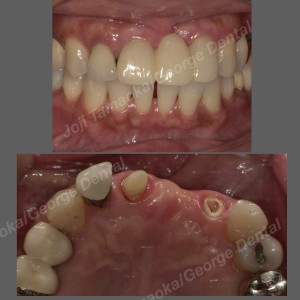

初診時の状況

ブリッジを除去すると、欠損部(抜歯した部分)の歯ぐき=歯槽堤が大きく萎縮していることが判明。

歯ぐきの高さが不足していたため、ポンティック(ブリッジのダミーの歯)が長く作られており、笑った時の見た目に違和感が出ていました。